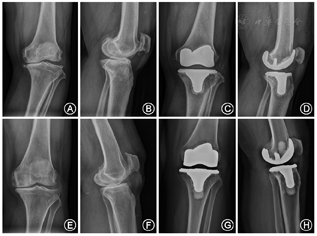

手术在神经阻滞麻醉或全身麻醉下进行,全程使用止血带。所有病例均为前正中切口的内侧髌旁入路显露,切断前交叉韧带,部分松解挛缩组织,股骨侧采用髓内定位,截除股骨远端骨质9 mm,髁间截骨仅去除薄片骨质。CR组保留PCL,CS组则切除PCL。胫骨侧采用髓外定位,内翻膝定位外侧平台截骨,外翻膝则定位内侧平台截骨。两组均不置换髌骨,仅做髌周去神经化处理并修整髌骨关节面,试模测试关节稳定性及活动度后,骨水泥固定股骨和胫骨假体,植入相应垫片(图1)。两组术后处理方法一致,术后当天麻醉恢复良好后即开始进行股四头肌舒缩运动和踝泵运动,术后患膝每天2次冰敷,常规预防性抗生素48 h和预防性抗凝治疗,24~48 h拔除引流管后即开始主被动屈伸膝功能及股四头肌力量康复锻炼,并借助助行器开始下地负重行走练习。出院后通过定期门诊复查或电话继续指导患者康复锻炼,嘱定期复查X线片(图2)。